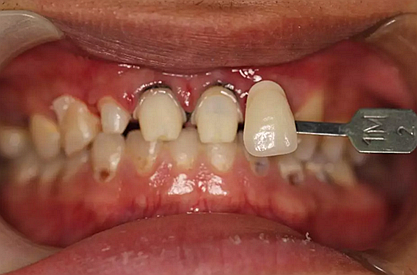

下面是醫(yī)生眼中和ct下的我們

一身病痛啊

牙結(jié)石、牙齦炎癥、牙體殘缺、慢性牙髓炎、蛀牙......

兩周后,主人帶我們往醫(yī)院拆線,取模,比色,為我們重新量身定制了一套堅固的“外套”。